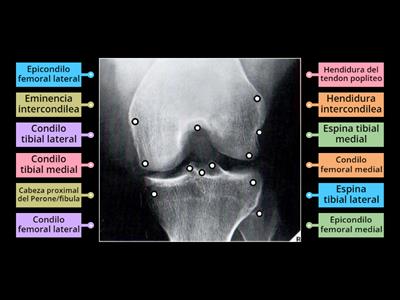

Anatomia rx tunel intercondilio rodilla